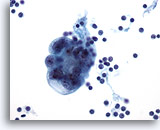

Peritoneal effusion: Metastatic carcinoma of the breast. Many small clusters and single malignant cells contrast with benign mesothelial cells. 20X

Peritoneal effusion:

Metastatic carcinoma of the breast. Many small clusters and single malignant cells contrast with benign mesothelial cells.

20X